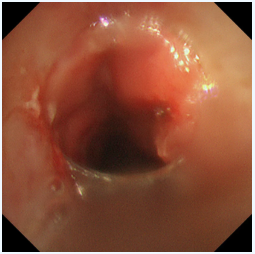

患者王先生(化名),20多年前因喉癌接受了喉切開手術(shù),長期留置氣管套管。一周前,他再次感受到熟悉的窒息感——呼吸困難加劇,喉間痰鳴,卻有痰咳不出,每一次吸氣都異常費力,家人緊急將他送至瑞康醫(yī)院救治。經(jīng)檢查,王先生的氣道出現(xiàn)了嚴(yán)重的增生性狹窄。新生的肉芽組織像藤蔓一樣在主氣道內(nèi)生長,使得原本就不寬敞的呼吸道變得更加狹窄,最嚴(yán)重處堵塞程度超過50%。這不僅是導(dǎo)致他呼吸困難的直接原因,也使得分泌物無法排出,易引發(fā)肺部感染和呼吸衰竭,情況萬分危急。

激光灼蝕,精準(zhǔn)“開路”:在氣管鏡引導(dǎo)下,首先利用高頻激光對堵塞氣道的增生組織進行精準(zhǔn)、迅速地汽化切割。激光如同一位技藝高超的“雕刻師”,快速清除掉大部分梗阻物,為后續(xù)治療打開一個通暢的“窗口”,迅速緩解患者的窒息風(fēng)險。